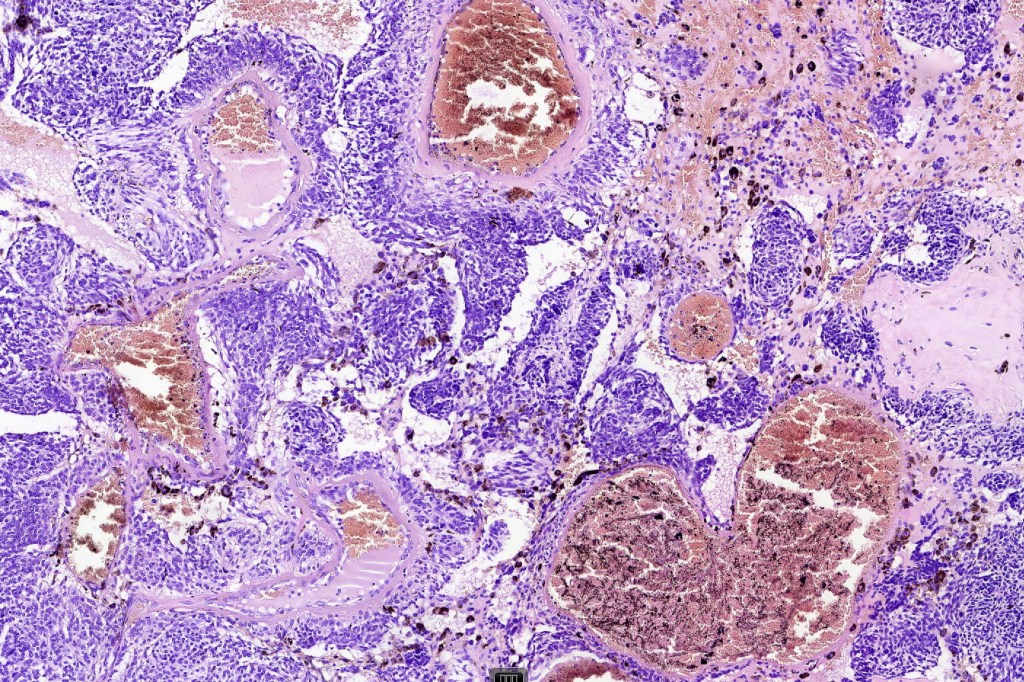

•Most characteristic is the dumbbell silhouette although a plague morphology may also be encountered

•Admixture of spindle cells, pigmented bipolar or dendritic cells & melanophages

•Cytoplasm is pale and nuclei are small with inconspicuous nucleoli

•An alveolar pattern is characteristic particularly with clear cell nodules

•Multinucleate giant cells sometimes present

•Stromal fibrosis, myxoid change, vascular hyalinization with cyst formation are often seen